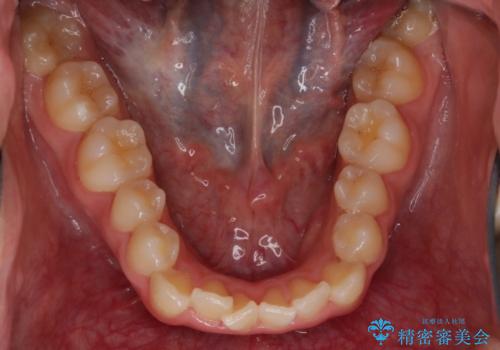

症状としてはオープンバイト(開咬)があり、舌癖も見られました。

日常的に舌を歯に押し付ける癖に対しては舌のトレーニングも併せて行うことで、矯正治療の効率化を図ると同時に後戻りのリスクを最小限に抑えるようにしました。

舌癖がある方は、歯を内側から押し出す力が日常的に働くため、矯正治療後も歯と歯の隙間が開いてしまうなどの後戻りのリスクが高いことが知られています。舌の正しいポジショニングやお口周りの筋肉のトレーニングを行うことで後戻りのリスクを減らすことが可能です。

お口周りの筋肉を鍛えることで、首周りもスッキリさせる効果が期待できます。